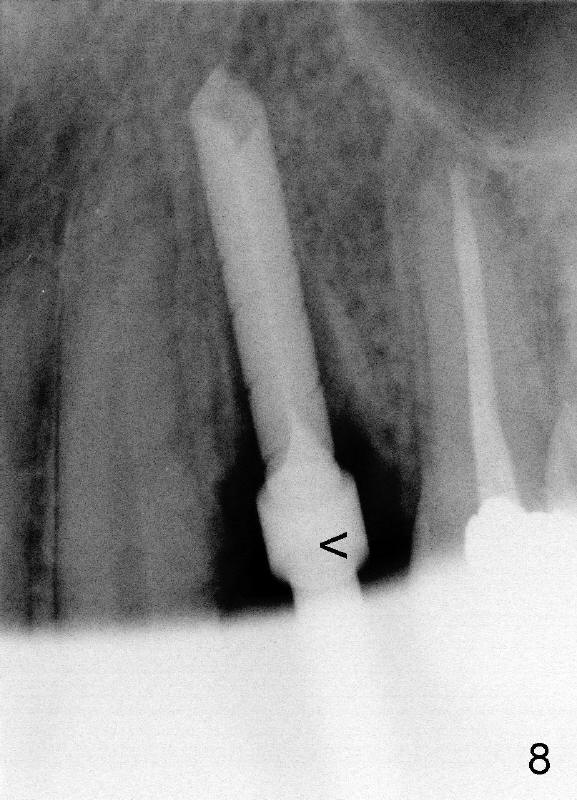

After tooth extraction, the osteotomy is initiated in the palatal socket (compare Fig.6,7 (CBCT, not the same case) with a pilot drill (pink outline). The osteotomy is enlarged by a series of reamers until the apical diameter (3.5 mm, Fig.8) of the prospective tapered implant (5x20 mm, Fig.9 I). The socket is obliterated by the tapered implant (Fig.9) with simultaneously achieving primary stability. This looks less over engineering than the first case.